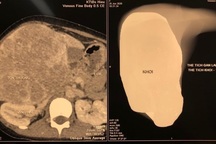

Ung thư gan giai đoạn đầu hầu như không có triệu chứng lâm sàng. Một số dấu hiệu để nhận biết sớm bệnh ung thư gan gồm: chán ăn, mệt mỏi, đầy bụng chậm tiêu, sụt cân nhiều trong thời gian ngắn; vàng da, vàng mắt; hay đau ở vùng dưới bờ sườn bên phải; táo bón hoặc tiêu chảy; đau vùng vai phải…

Khi bệnh tiến triển u gan to thì có thể sờ thấy gan to dưới bờ sườn phải, mũi ức.